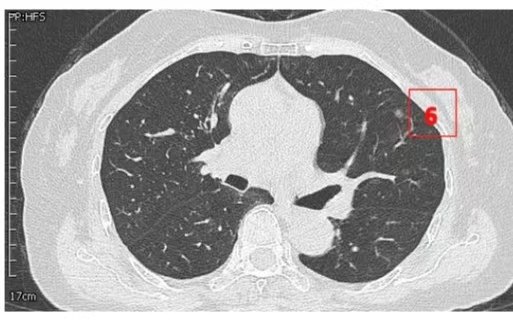

患者女性,71岁,因“发现左肺多发结节2周”入院。胸部CT提示左肺多发磨玻璃结节,较大者位于左肺上叶,呈类圆形,边界清晰,最大直径约9mm。该CT表现高度提示恶性可能。鉴于患者结节数量较多,为减少术中肺组织损伤,术前于CT引导下行经皮肺结节定位术,继而实施胸腔镜下左肺楔形切除术。术中共切除肺部结节6枚。术后病理示:左肺上叶较大结节(4号)为微浸润腺癌,其余5枚结节均为原位癌。患者术后恢复良好,于术后第1天拔除胸腔引流管,第4天顺利出院。

▲定位操作